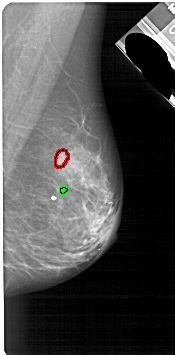

A_1791_1.LEFT_MLO

LEFT_MLO LINES 5356 PIXELS_PER_LINE 2626 BITS_PER_PIXEL 12 RESOLUTION 43.5 NON_OVERLAY

FILE: A_1791_1.RIGHT_MLO.OVERLAY

TOTAL_ABNORMALITIES 1

ABNORMALITY 1

LESION_TYPE CALCIFICATION TYPE PLEOMORPHIC DISTRIBUTION CLUSTERED

ASSESSMENT 4

SUBTLETY 2

PATHOLOGY BENIGN

TOTAL_OUTLINES 1

BOUNDARY

ABNORMALITY 2